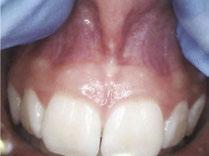

Airway health and young children – one case

Over 10 years ago, we began Orthotropic® treatment for a 5 year, 3-month-old boy with a diagnosis of Pierre-Robin Sequence, Obstructive Sleep Apnea (OSA), and Failure to Thrive (Figure 1). With lack of forward development of the face com-

monly seen in Pierre-Robin patients, his airway was compromised, resulting in OSA. The Failure to Thrive diagnosis likely resulted from insufficient growth hormone being released during the deeper stages of sleep. This treatment began before any permanent teeth erupted. Our goal was to eliminate OSA.

Orthotropics® uses removable appliances to laterally expand the upper arch while simultaneously advancing the upper anterior teeth to their proper place in the face. Then the mandible is developed forward. Orthotropics® is my preferred treatment in cases like this because it negates the head gear-effect producing better facial balance5 and also can result in substantial airway improvements (Figure 2).6

This young boy had great parental support and was very compliant during the treatment. A posttreatment sleep test showed no signs of sleep apnea.7 Failure to Thrive was also overcome. Now at 17 years old, this patient is 5 ft. 7in. tall and is still growing. I believe that improved breathing and sleep has resulted in an increase in HGH production which allowed him to resume normal growth. He’s an aggressive tennis player with a big smile and no return of his OSA (Figure 3). Thankfully, he’s an excellent student with no evidence of brain damage from his early OSA diagnosis.

Figure 1: Pretreatment gallery Figure 3: Today, he’s a tennis player Figure 2: Pre- and posttreatment airways